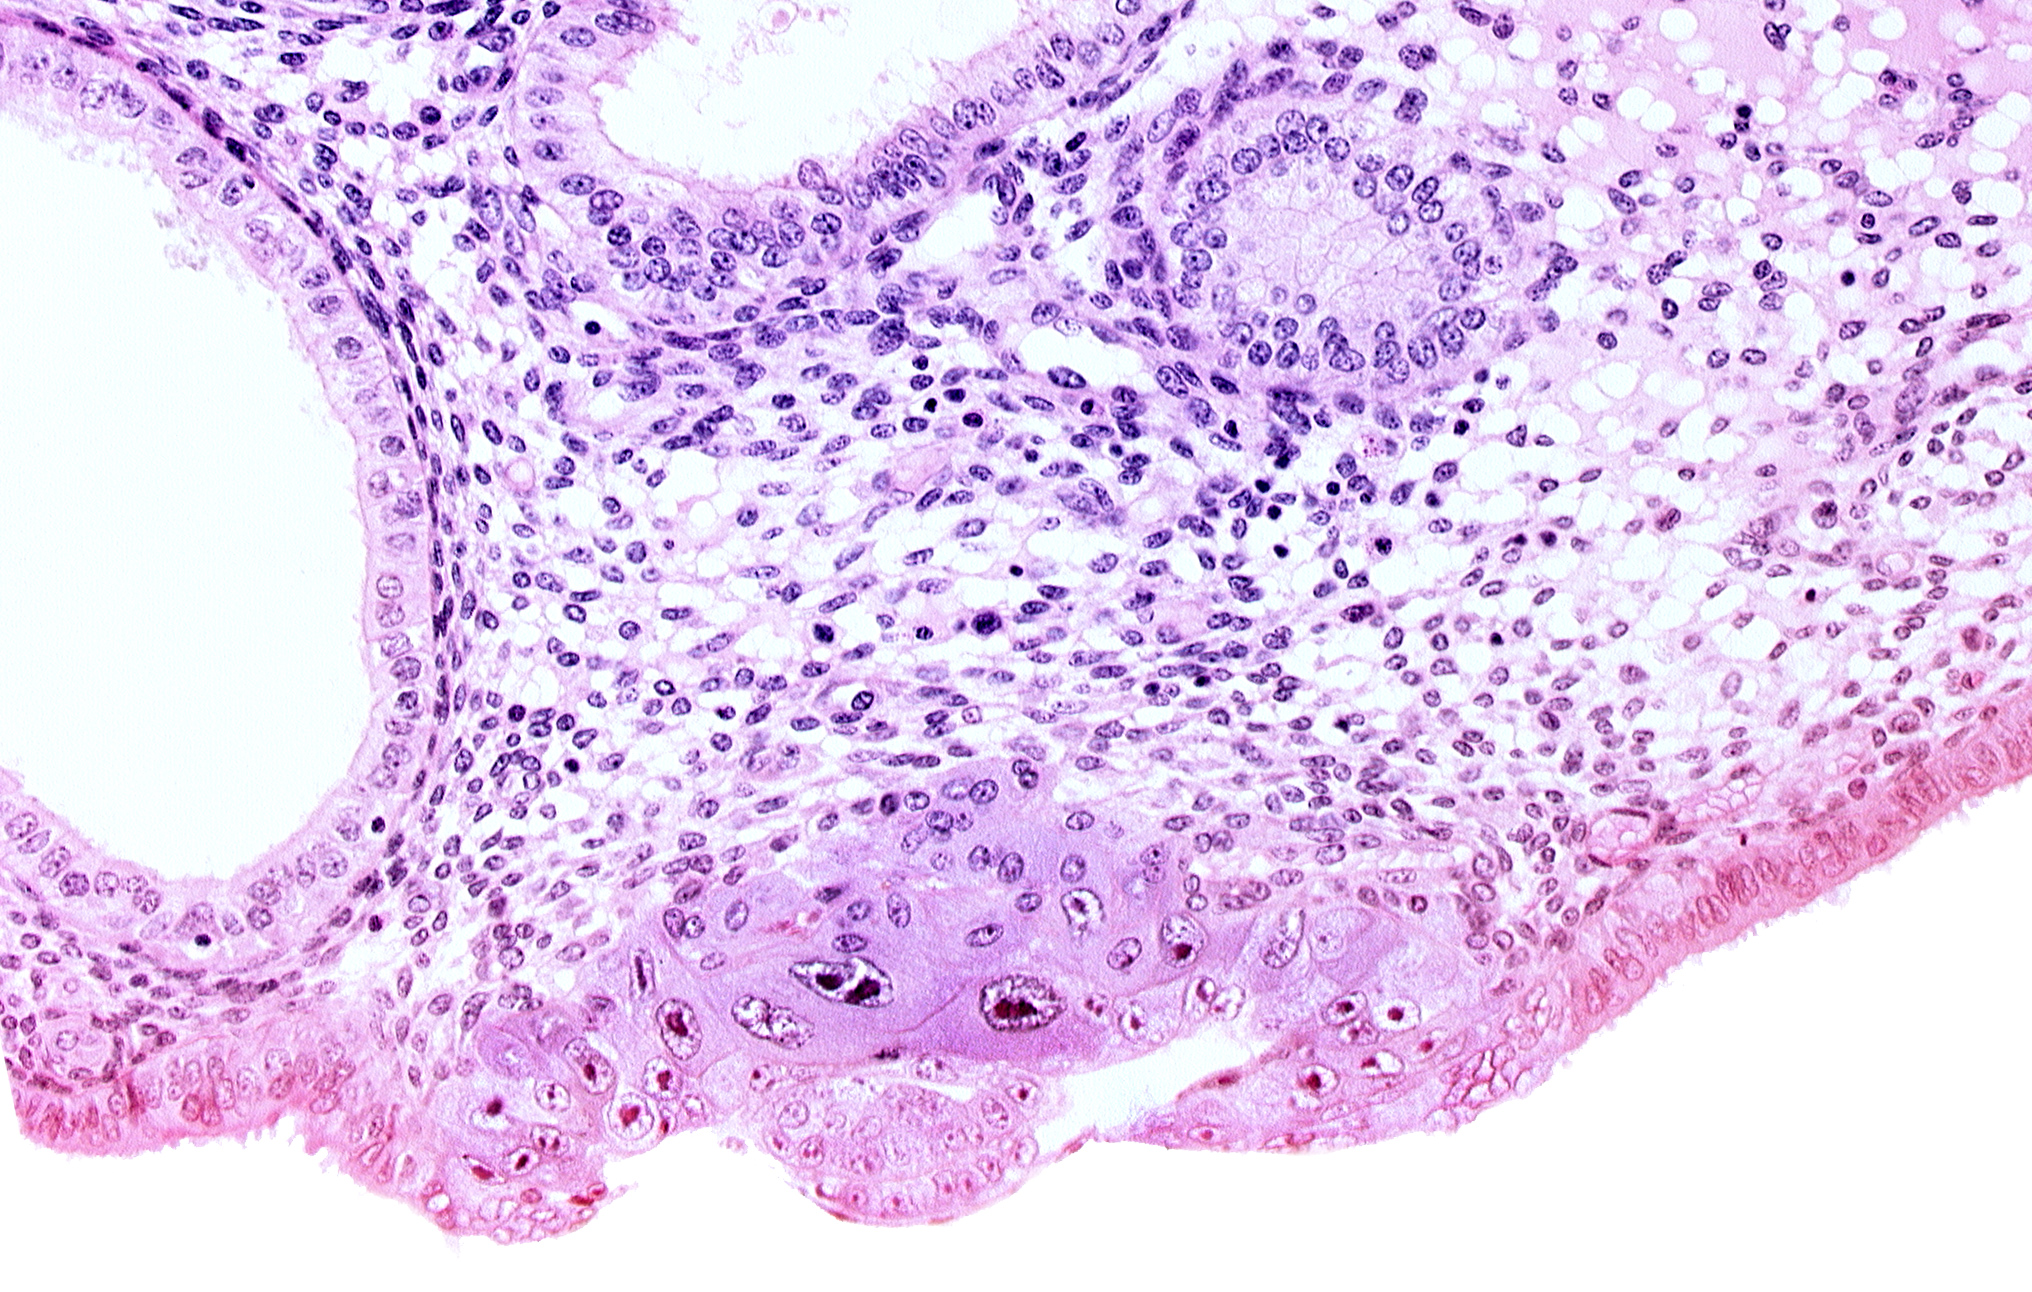

Carnegie Embryo #8020 | Location: 06-01-09

Keywords: amniotic cavity, blastocystic cavity (blastocoele), cytotrophoblast, embryonic disc, endometrial gland, endometrial sinusoid, solid syncytiotrophoblast, uterine cavity

Source: The Virtual Human Embryo.